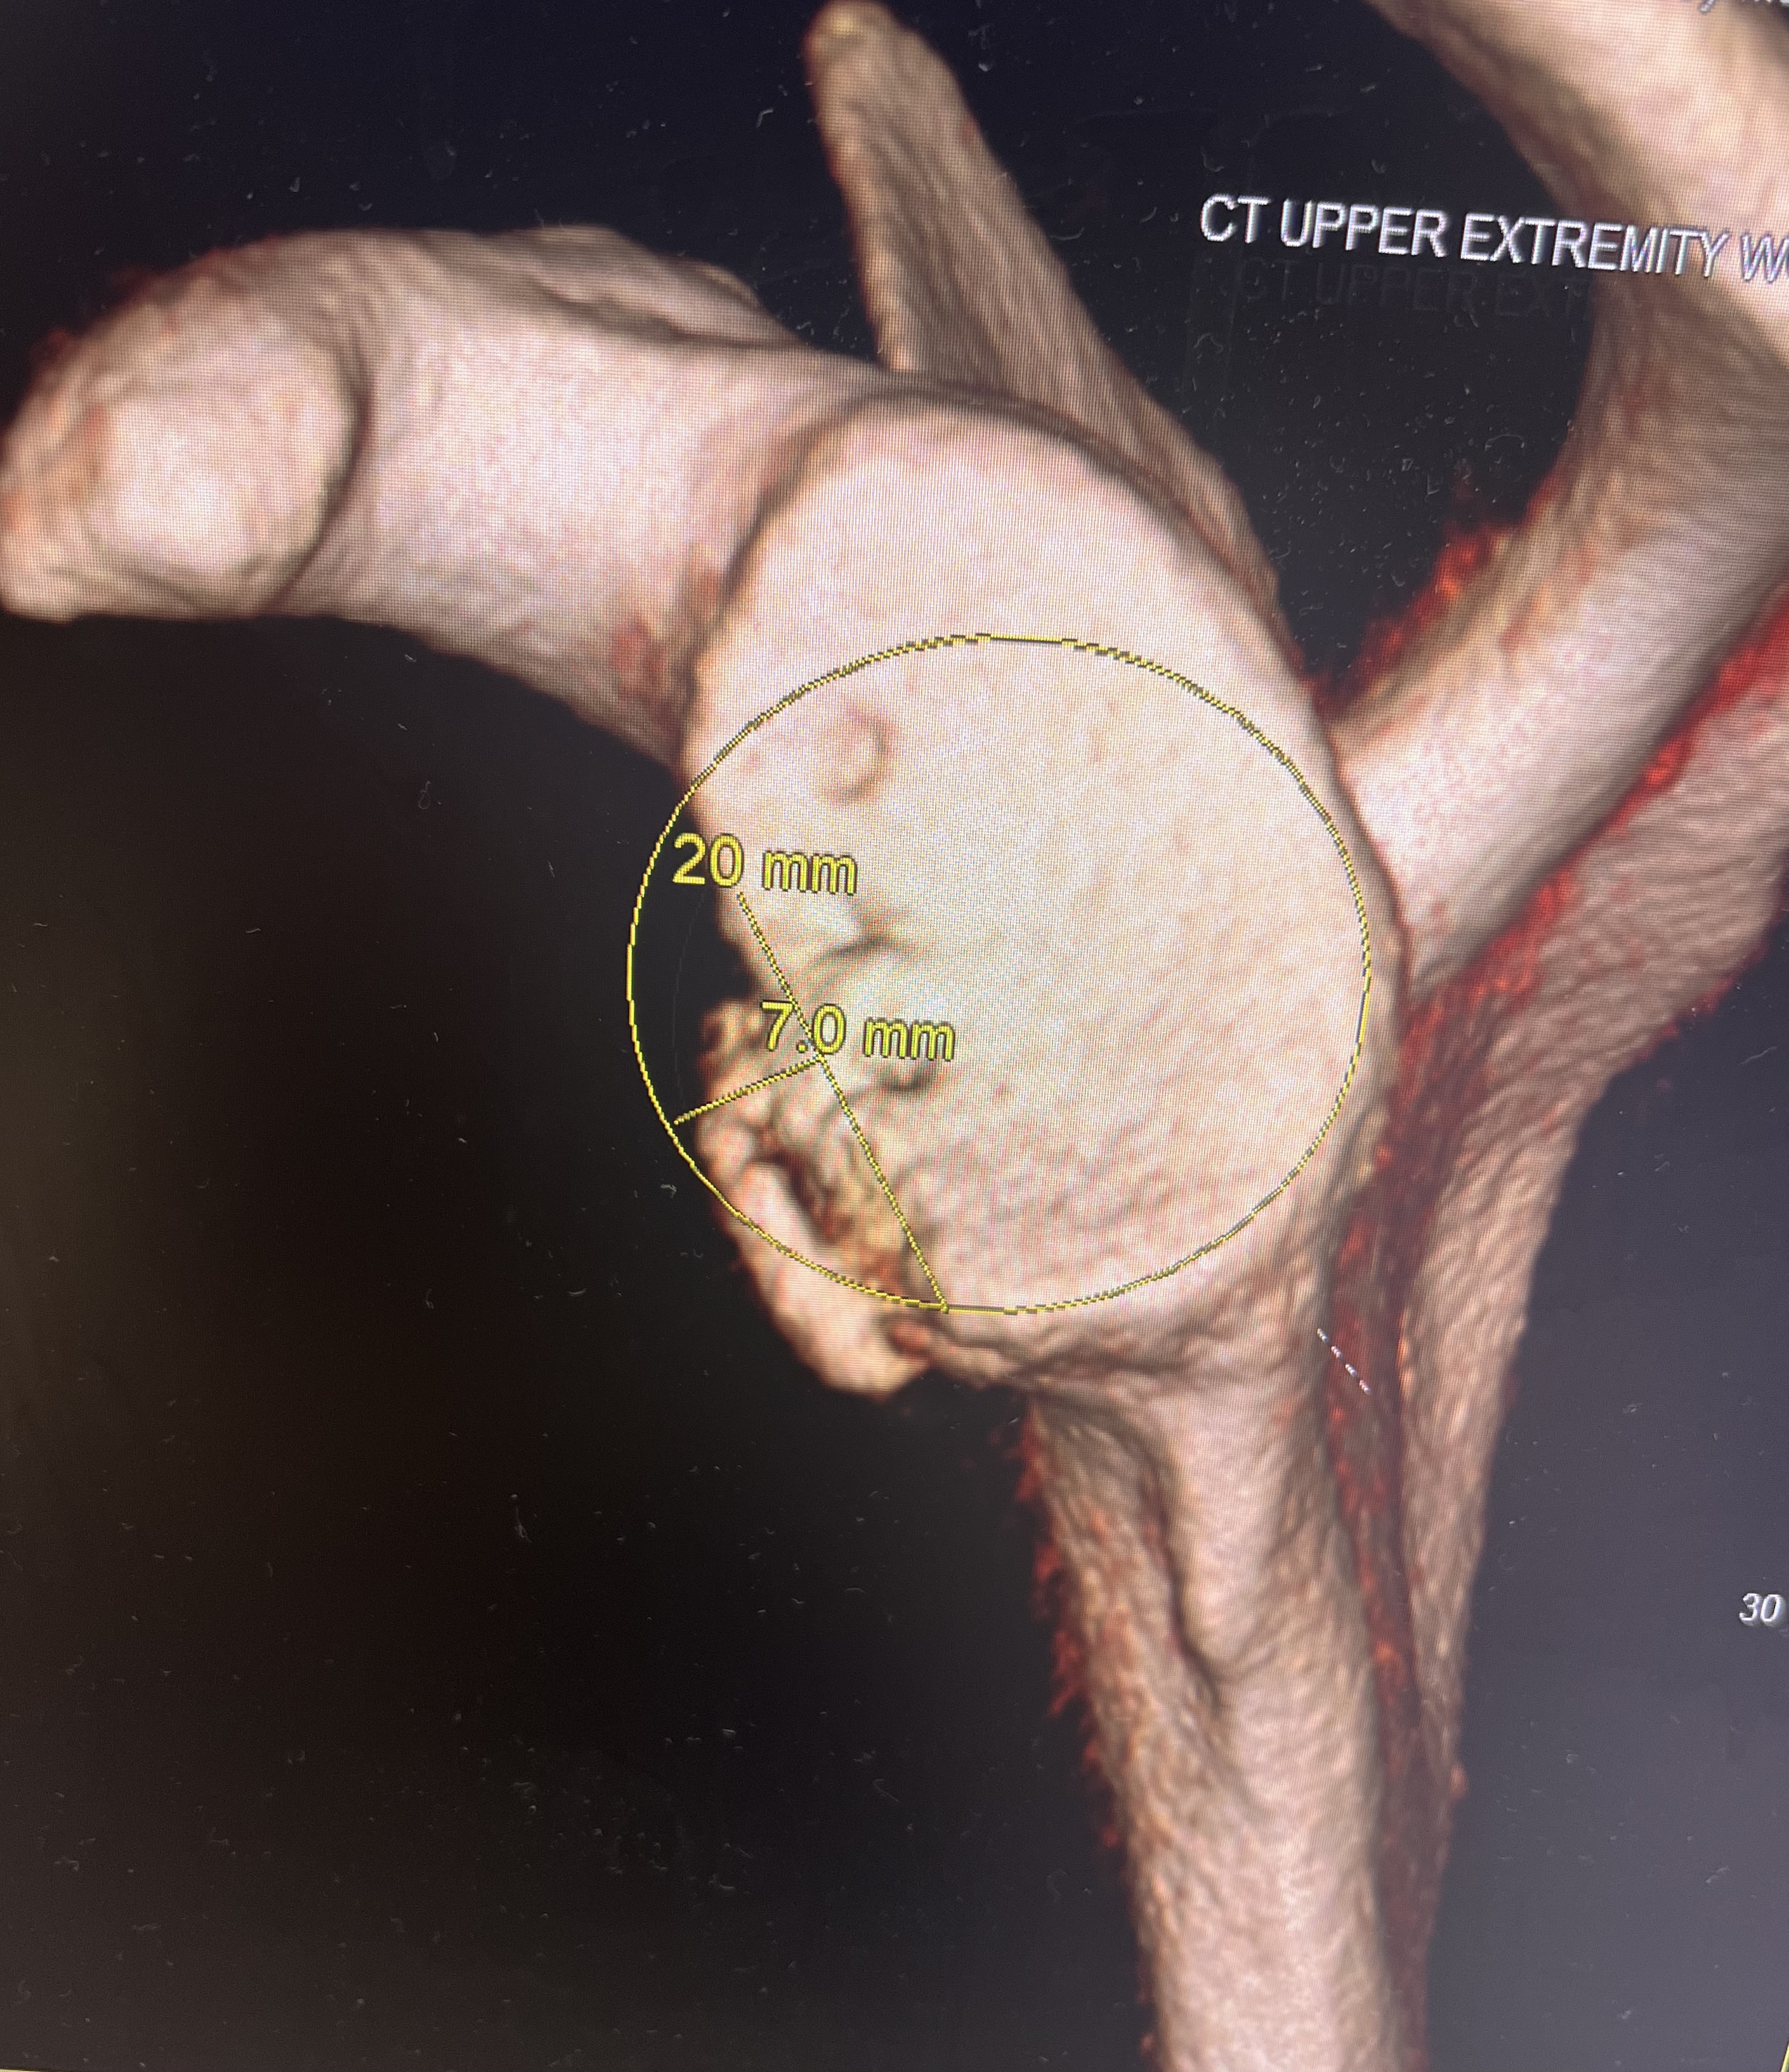

COR and the Iannotti Circle, part 2

THE SURGEON’S DUTIES how can surgeons better replicate the COR and the Iannotti Circle? In my last post, I presented information that lays out the importance of restoration of both the COR and the Iannotti circle in anatomic shoulder replacement. Related metrics, but separate. And both are likely important for optimizing outcomes of replacement. What… Continue reading

COR and the Iannotti circle

“A high position of the humeral component relative to the greater tuberosity was the most common problem with humeral component positioning” Franta, Lenters, Mounce, Neradilek, Matsen “SAFE” study JSES 2007 Glenoid side Shoulder surgeons have recognized the importance of glenoid component positioning in outcomes of anatomic shoulder arthroplasty. Many surgeons have bolstered their academic prowess… Continue reading